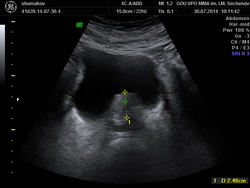

Из анамнеза: в июле 2014 года после физической нагрузки отметил появление крови в моче с бесформенными сгустками. В поликлинике по месту жительства при ультразвуковом исследовании выявлена аденома предстательной железы. Консультирован в клинике урологии УКБ№2 Первого МГМУ им. И.М. Сеченова, при УЗИ заподозрена опухоль мочевого пузыря. Выполнена МРТ органов малого таза, по данным которой по левой боковой стенке мочевого пузыря определяется экзофитное образование размерами 0,9х0,8х0,7мм. Также выявлена аденома предстательной железы. Госпитализирован в плановом порядке для оперативного лечения

Рис№1. УЗИ мочевого пузыря и предстательной железы.